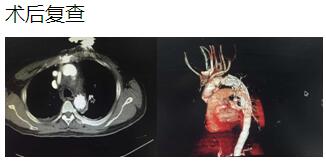

患者是一位48歲中年男性,因胸痛1小時(shí)入院,我院CT提示主動(dòng)脈夾層累及胸、腹主動(dòng)脈全層,診斷為主動(dòng)脈夾層(D ebaKey I型)?;颊卟∏槲V兀中g(shù)治療是挽救其生命的唯一希望。為了挽救病人生命,經(jīng)過麻醉科、手術(shù)室、體外循環(huán)組的術(shù)前充分討論,心胸外科廖金文主任、廖承輝副主任帶領(lǐng)團(tuán)隊(duì)決定為其施行復(fù)雜而高難度的淺低溫停循環(huán)下“孫氏手術(shù)”。術(shù)中見主動(dòng)脈全程及三分支受累,右冠受累,冠脈開口受壓狹窄,予以行“升主動(dòng)脈 主動(dòng)脈弓置換 降主動(dòng)脈術(shù)中支架置入術(shù)”,團(tuán)隊(duì)成員歷經(jīng)約10個(gè)小時(shí)的奮戰(zhàn),手術(shù)順利完成。術(shù)后六小時(shí)患者意識完全清醒,現(xiàn)在已完全康復(fù)。